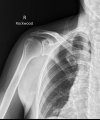

อาการไหล่ติดเนื่องจาก หินปูน ที่เอ็นกล้ามเนื้อหัวไหล่ ร่วมกับเอ็นหัวไหล่อักเสบ และมีการเยื่อหุ้มหัวไหล่ติดตึงครับ (Calcific Tendinitis)